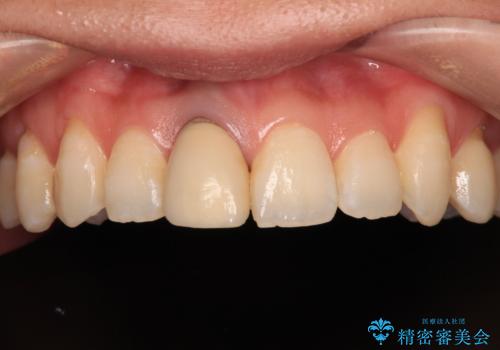

被せものと土台の歯との境目が、歯茎の下に隠れるように調整し、段差もないため、審美性・清掃性のどちらの観点からも理想的な被せものになり、患者様は満足されました。